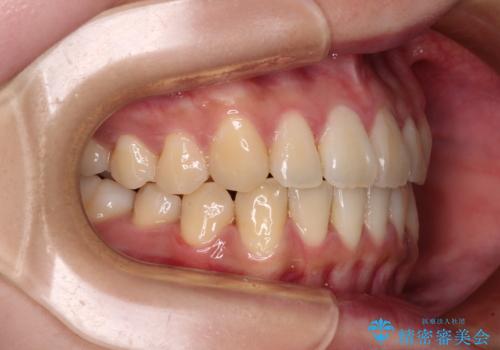

- 前歯の捻れを気にして来院された患者様です。

上顎前歯が捻れて前方に飛び出しており、下顎前歯もそれに沿うようにデコボコとなっていました。

IPR(歯と歯の間を削る処置)によりスペースを獲得して下顎前歯のデコボコを改善し、上顎前歯は下顎前歯と接する位置にまで引っ込めるように設定し、インビザラインにて矯正治療を行うこととしました。